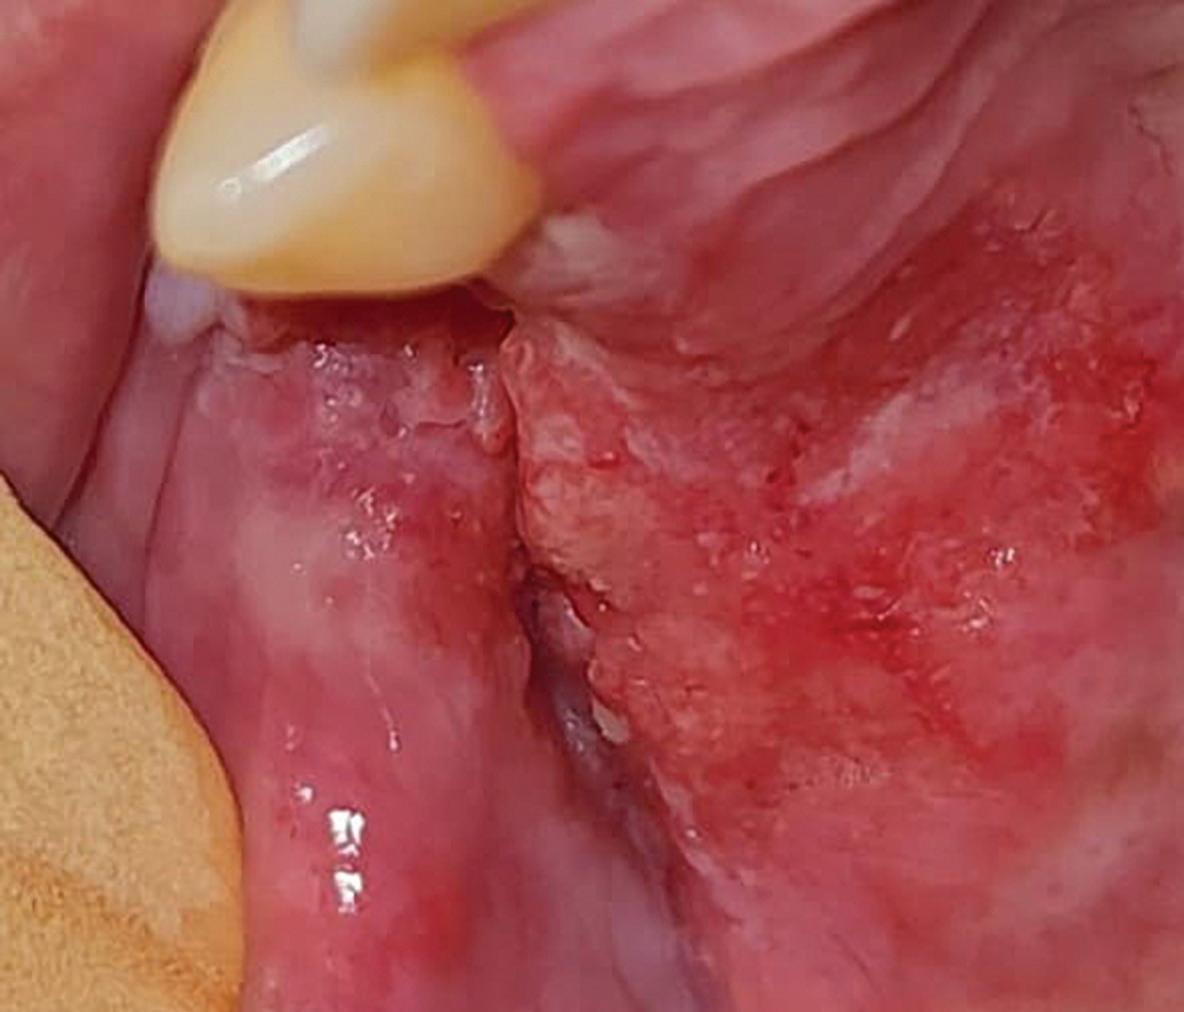

Malignant transformation of oral lichen planus after 6 years: a case report

Alessandro Antônio Costa Pereira